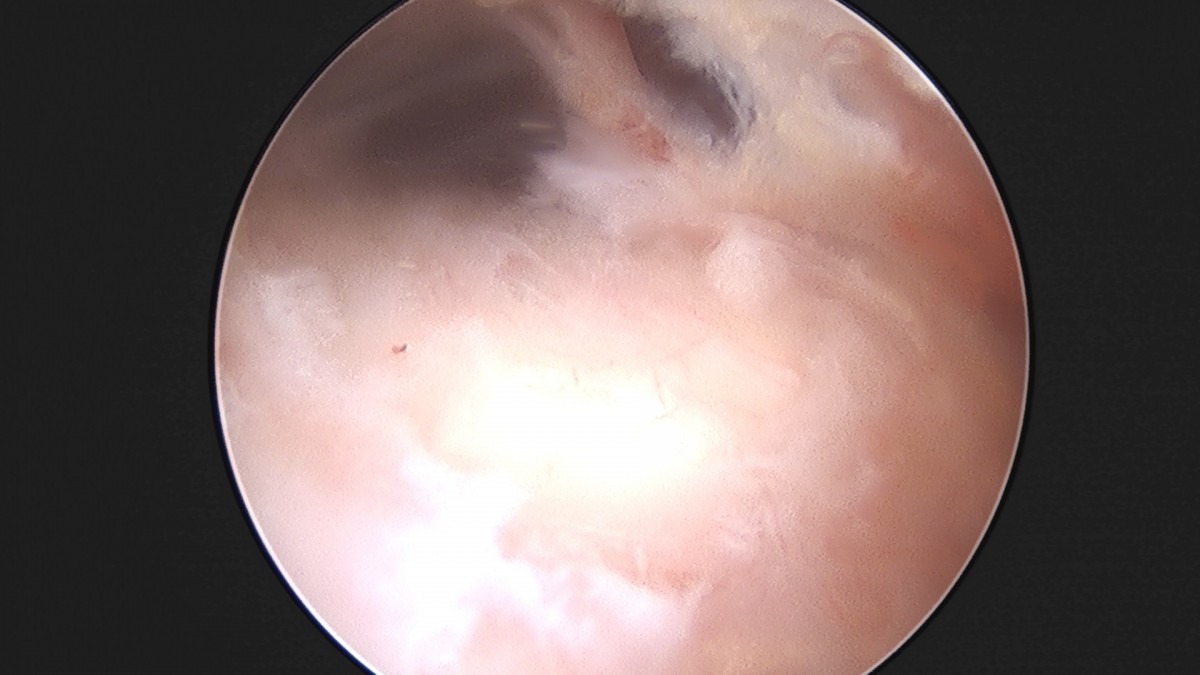

이재상원장님 어깨 견봉하 감압술 이승O 환자

작성자 최고관리자 댓글 0건 조회 806회 작성일 25-09-16 15:26